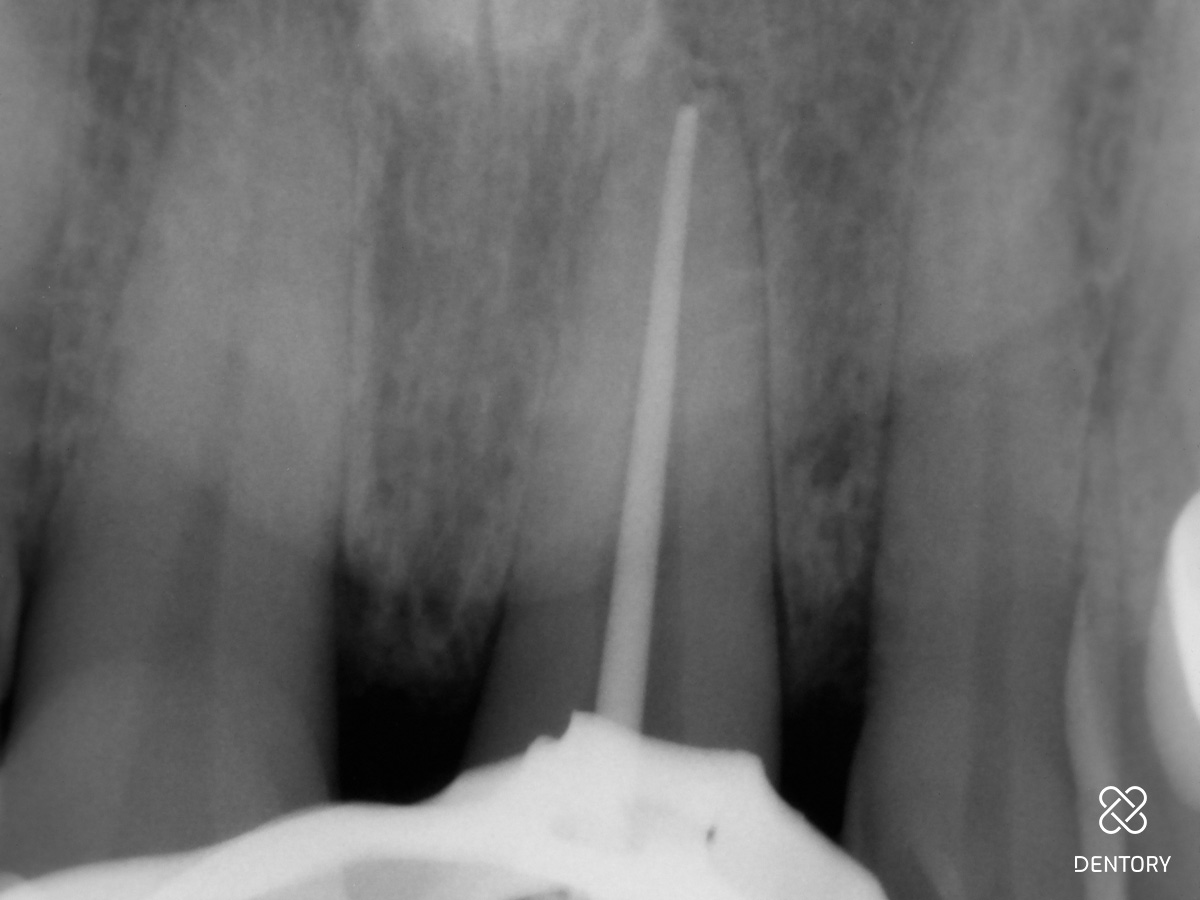

Abbildung 6

Maschinelle NiTi-Revisionsfeile bis Sicherheitslänge 21 mm in den Kanal einführen.